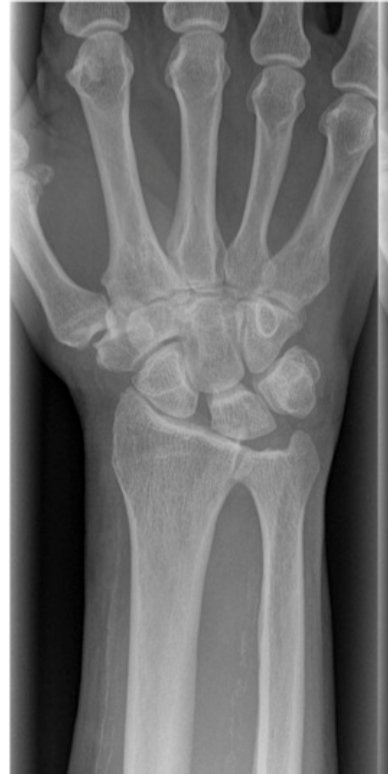

Fall onto an outstretched hand

A gap there...

What is the sign?

Gaptooth sign in scapho-lunate ligament rupture

Also called Terry-Thomas sign

an increase in the scapholunate space on an AP radiograph of the wrist (or coronal CT)

πŸ‘‰ increased distance indicates scapholunate dissociation (often with rotary subluxation of the scaphoid) due to ligamentous injury

There is no consensus as to what measurement constitutes widening, but a cut-off of 3 or 4 mm is reasonable in most cases